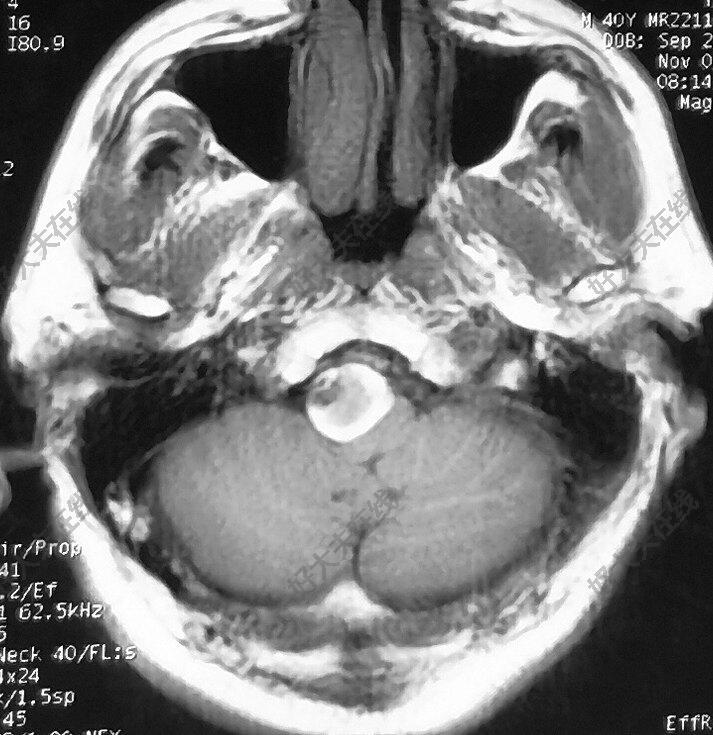

治療前 椎動(dòng)脈巨大動(dòng)脈瘤,嚴(yán)重壓迫腦干,頭痛明顯,視物重影,已經(jīng)臥床半個(gè)月。 治療中 心瑋密網(wǎng)支架(4.5mm*30mm)一枚置入,彈簧圈一枚促進(jìn)動(dòng)脈瘤內(nèi)血栓盡快形成。 治療后 治療后2天 頭痛明顯緩解,視物重影消失,已經(jīng)能下地活動(dòng)。順利出院繼續(xù)回家康復(fù)鍛煉。